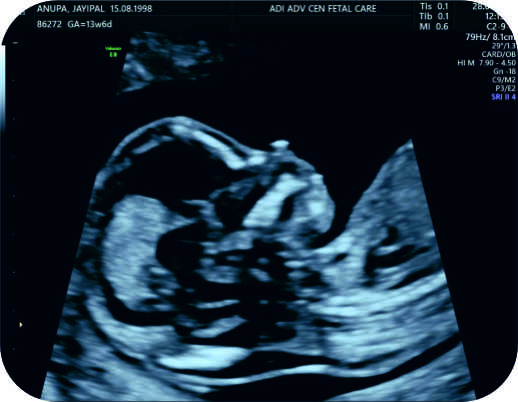

Photo Gallery CT Machine ICU Modular OT Private Ward General Ward USG Fetal 3D Fetal Intervention 1 Fetal Intervention 2